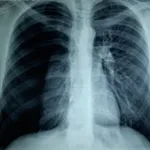

Akciğer ve göğüs boşluğu travmaları

Göğüs boşluğunda ve akciğerlerde en çok görülen travma türleri han­gileridir ?

a.Göğüs boşluğunun ciddî surette ezilmesi.

b.Çatlayan kaburgalar veya çatlayan göğüs kemiği (sternum).

c.Kınlan bir kaburganın akciğere girmesiyle bir ciğerin yaralan­ması.

d.Akciğer etrafındaki plevral boşluğu hava, kan veya ikisinin de birden girmesiyle. Bu durum bir ciğer zedelenmesinden veya ya­bancı bir cismin göğüs boşluğuna girmesiyle meydana gelebilir.

e.Kendi kendine olma bir kopmadan veya kanamadan sonra bir ciğerin çöküntü göstermesi (sönmesi).

f.Göğüse isabet eden bıçak veya kurşun yaraları.